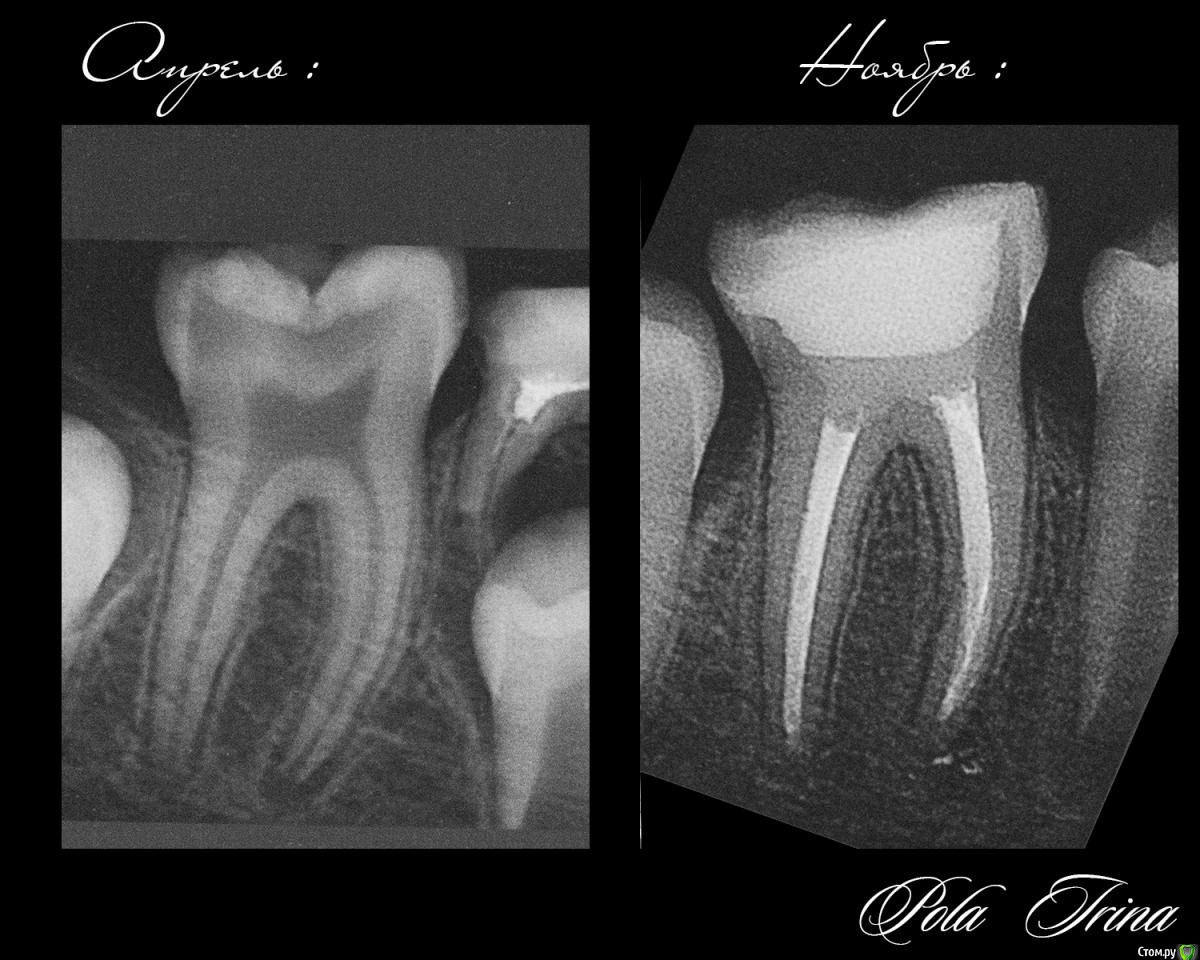

M@estro Опубликовано 3 апреля, 2015 Поделиться Опубликовано 3 апреля, 2015 (изменено) Как она успевает за раб. день принять 15 детей? Да еще с коффером и бубном? Если это лечение,а не exstr молочныхзубов,то нереально.]5-6 детей принимаешь и сильно устаешь,больше для врача тяжело,качество будет не то. Такая нагрузка для героев! Молодец! Она успевает. Она молодец ! Вот , доказательства : http://s018.radikal.ru/i504/1504/b3/7d3af1f11614.jpg http://s017.radikal.ru/i400/1504/61/c641d8bd285c.jpg Изменено 3 апреля, 2015 пользователем M@estro 9 Ссылка на комментарий

CRAZYDUCK Опубликовано 21 сентября, 2015 Поделиться Опубликовано 21 сентября, 2015 (изменено) http://s020.radikal.ru/i713/1509/6e/6af33d606cc5.jpgСпасибо большое коллегам за советы по коффердаму ( особенно Танюше!), работать с коффердамом просто классно !!!! удобно и быстро , детям он тоже нравится, доктора , не бойтесь его осваивать ! Здесь правда мальчик "большой"- 6 лет, но все же - кариес 5.5 ,пульпит 5.4, сначала кламп поставила KSK для 5.5 зуба , потом платок , потом рамку , фото не очень много, но мне неудобно без ассистента , еще фотоаппарат долго "думает" почему-то.( снимок RVG 5.4, 5.5 до лечения).P.S. Лечила этого мальчишку в конце февраля ( кариес 8.4 и пульпит 8.5), были эти кариозные полости ( на 5.5 и 5.4 зубах уже тогда), но так как у меня срок родов был в марте , работать уже было тяжело и запись была большая , отправила их к коллеге ( лично его не знаю , но отзывы хорошие были), вот полечили они у этого доктора эти кариесы в мае , а в сентябре пришлось перелечить... Изменено 21 сентября, 2015 пользователем CRAZYDUCK 4 Ссылка на комментарий